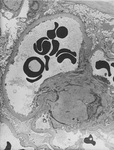

Doença renal diabética

Doença renal diabética: expansão mesangial decorrente do aumento da matriz mesangial e da redução da degradação do colágeno glicosilado

Do acervo do Dr. Raoul Fresco; usado com permissão